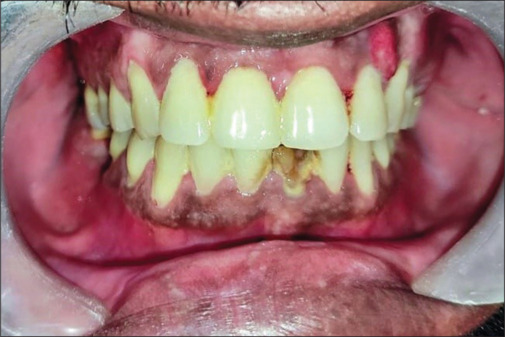

牙髓-牙周(根管-牙周)病变在牙科诊所很常见,患者通常表现为急性牙髓疼痛,常常伴有脓肿形成和牙齿移动。治疗方法一般包括根管治疗(RCT),必要时进行外科手术。本文讨论的是一个值得注意的病例,患者是一名 43 岁的男性,主诉是左上背部疼痛和牙齿松动已持续 3 周。患者接受了一期牙周治疗,随后对 21 号至 25 号牙齿进行了 RCT 治疗。然而,2 周后,患者出现肿胀,于是进行了手术切除和活检。组织病理学分析表明,该病菌为无隔膜的菌丝,具有直角分支,显示为粘孢子菌病。

Endodontic-periodontal (endo-perio) lesions are commonly encountered in dental clinics, with patients typically presenting with acute pulpal pain, often accompanied by abscess formation and tooth mobility. Management generally involves root canal treatment (RCT) and, if required, surgical intervention. This article discusses a notable case of a 43-year-old male patient who presented with a chief complaint of pain and loose teeth in the upper left back region for the past 3 weeks. Phase I periodontal therapy was initiated, followed by RCT of teeth #21 to #25. However, 2 weeks later, the patient presented with swelling, prompting surgical excision and biopsy. Histopathological analysis revealed nonseptate hyphae with right-angle branching, indicative of mucormycosis.